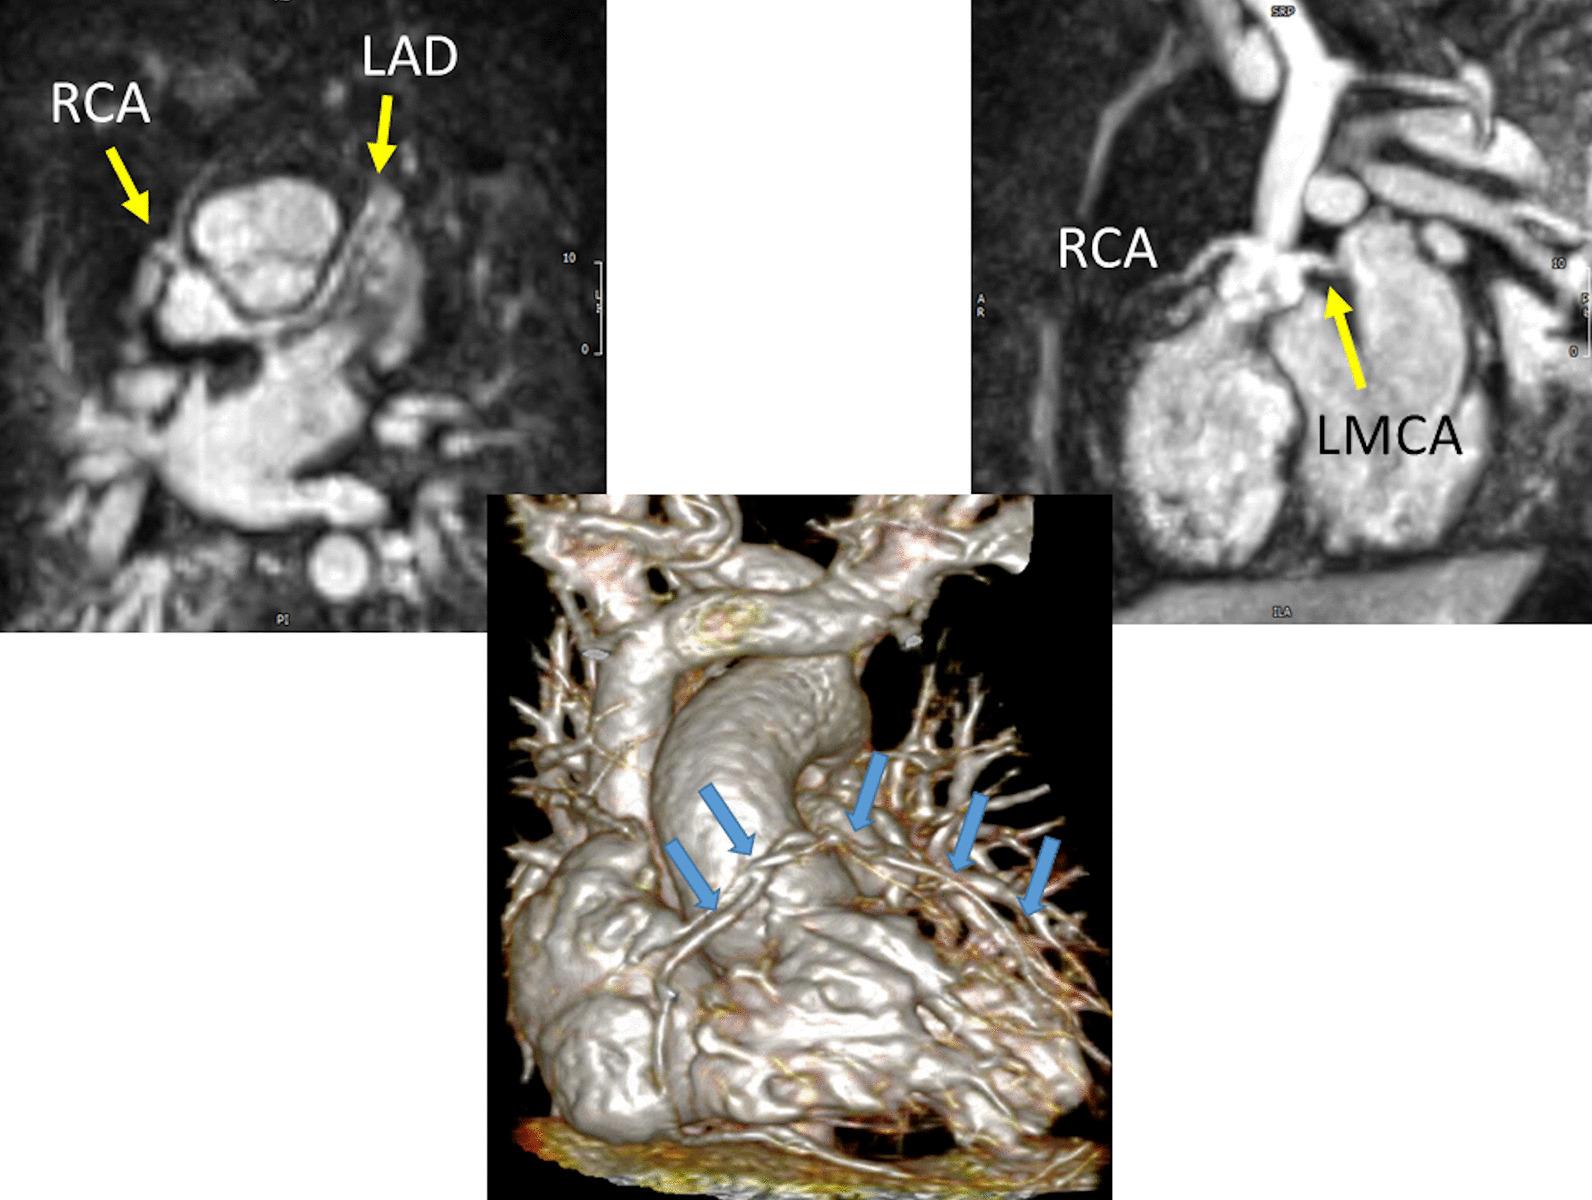

Cardiovascular magnetic resonance (CMR) has been utilized in the management and care of pediatric patients for nearly 40 years. It has evolved to become an invaluable tool in the assessment of the littlest of hearts for diagnosis, pre-interventional management and follow-up care. Although mentioned in a number of consensus and guidelines documents, an up-to-date, large, stand-alone guidance work for the use of CMR in pediatric congenital 36 and acquired 35 heart disease endorsed by numerous Societies involved in the care of these children is lacking. This guidelines document outlines the use of CMR in this patient population for a significant number of heart lesions in this age group and although admittedly, is not an exhaustive treatment, it does deal with an expansive list of many common clinical issues encountered in daily practice.

心血管磁共振(CMR)在儿科患者的管理和护理中已经应用了近 40 年。它已经发展成为评估最小的心脏的宝贵工具,用于诊断、介入前管理和随访。尽管在许多共识和指南文件中提到,但在儿科先天性心脏病和后天性心脏病领域,目前还缺乏一份由众多参与儿童护理的学会共同认可的、最新的、独立的、针对 CMR 使用的大型指南。本指南文件概述了 CMR 在该年龄段的许多心脏病变中的应用,尽管不能说是详尽的治疗方法,但它确实涉及了在日常实践中经常遇到的许多常见临床问题的广泛列表。